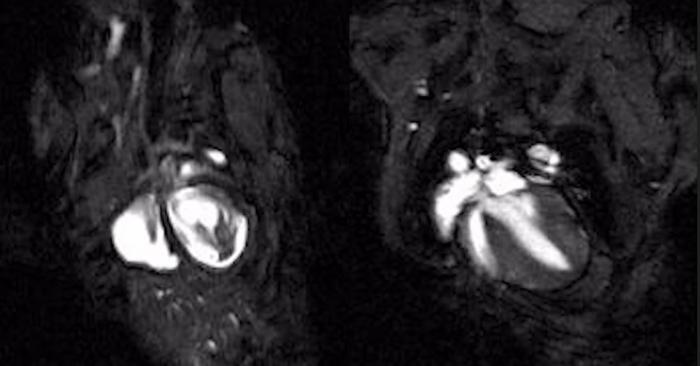

Cardiac magnetic resonance imaging (MRI) videos of beating hearts in an inherited arrhythmogenic cardiomyopathy mouse model, shown untreated (Left) and after connexin-43 gene therapy treatment (Right), illustrating repair of impaired heart function.